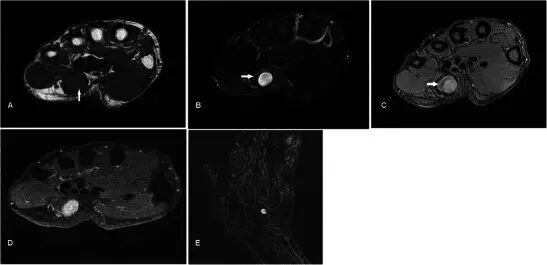

痛风Gout 痛风石可呈现多个局灶。 平片通常可以诊断。 具有突出边缘和相关联的钙化的软组织肿块,近关节侵蚀是典型的征象(图22A)。 痛风石的MRI表现也相当的特点, 病灶在所有MR序列上具有低至中间的信号,主要是由于钙化的存在并且可以显示外周增强[56](图22b-d)。

图22.在一个60岁的男性患有痛风的痛风,已知痛风,呈现为6个月的逐步肿胀沿左腕的尺骨方面。 (a)平片显示邻近尺骨茎突的无定形钙化(箭头)。 (b)T1w序列显示低信号(箭头)的不规则小叶质量。 (c)病灶在T2w-FS序列上也是低信号。 (d)看到轻微的外周增强,并且还存在下面的尺骨茎突的侵蚀(箭头)

肌腱异常Tendon abnormalities 腱鞘炎是指腱和腱鞘的炎症。 局部炎症可以临床上出现质量样。 腱鞘炎的MRI发现包括腱鞘内的流体信号增加,腱鞘扩张,滑膜增殖和增强(图23)。 根据一项研究,由MRI诊断的手的屈肌腱鞘炎是早期类风湿性关节炎的强预测因子[57]。

图23.腱鞘炎在24岁女性中具有1个月的肿胀,疼痛和在左食指的屈肌方面的运动范围的损失。 (a)T1w序列显示食指的屈肌腱鞘的扩散增厚(箭头)。 (b)T2w-FS序列显示指示水肿的屈肌腱鞘的增厚和增加的信号。 (c)缓慢增强